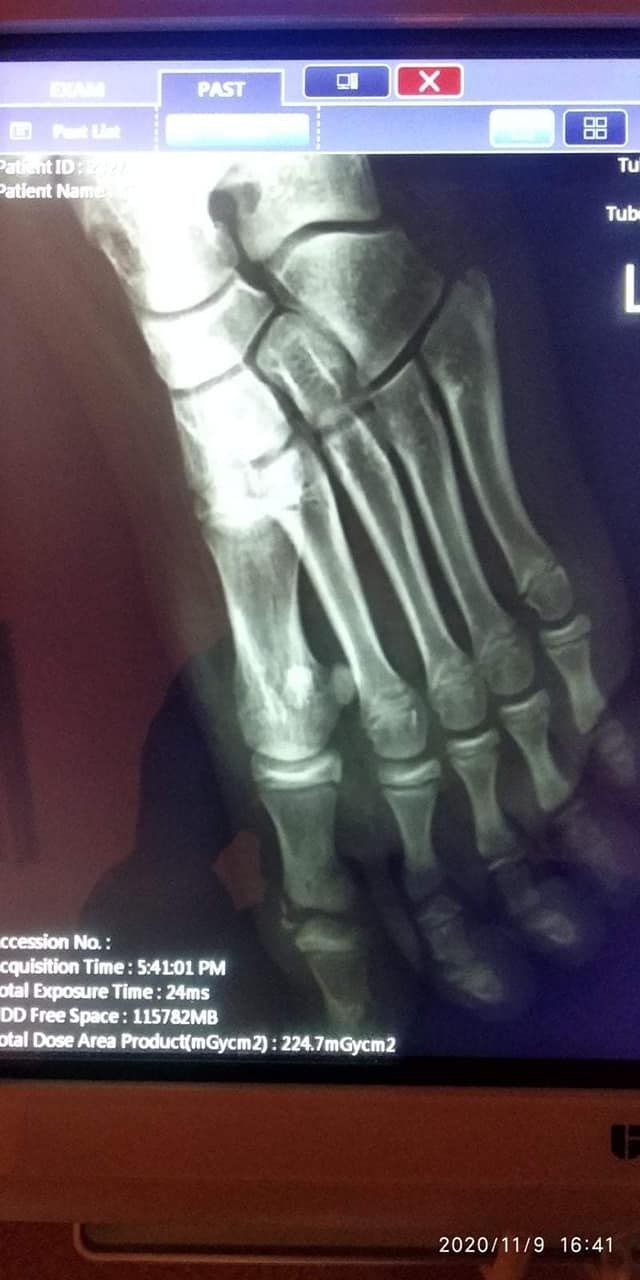

На территории днепровской школы №87 (ж/м Игрень) на маленькую Маргариту Кинько упал кусок бетонного забора. Девочка получила травму, идя со школы домой.

Сначала перелом, потом неправильно установленный гипс. Это привело к очень плохим последствиям, отмирают ткани. Идёт борьба за не удаление пальцев ноги, - пишет в своем посте Ксения Пантюшкина.

Мама школьницы Надежда Кинько рассказывает, сейчас девочка чувствует себя лучше и даже начала кушать. До этого у нее была температура, рвота и головная боль. После полученной травмы ей предстоит длительный курс лечения и восстановления.